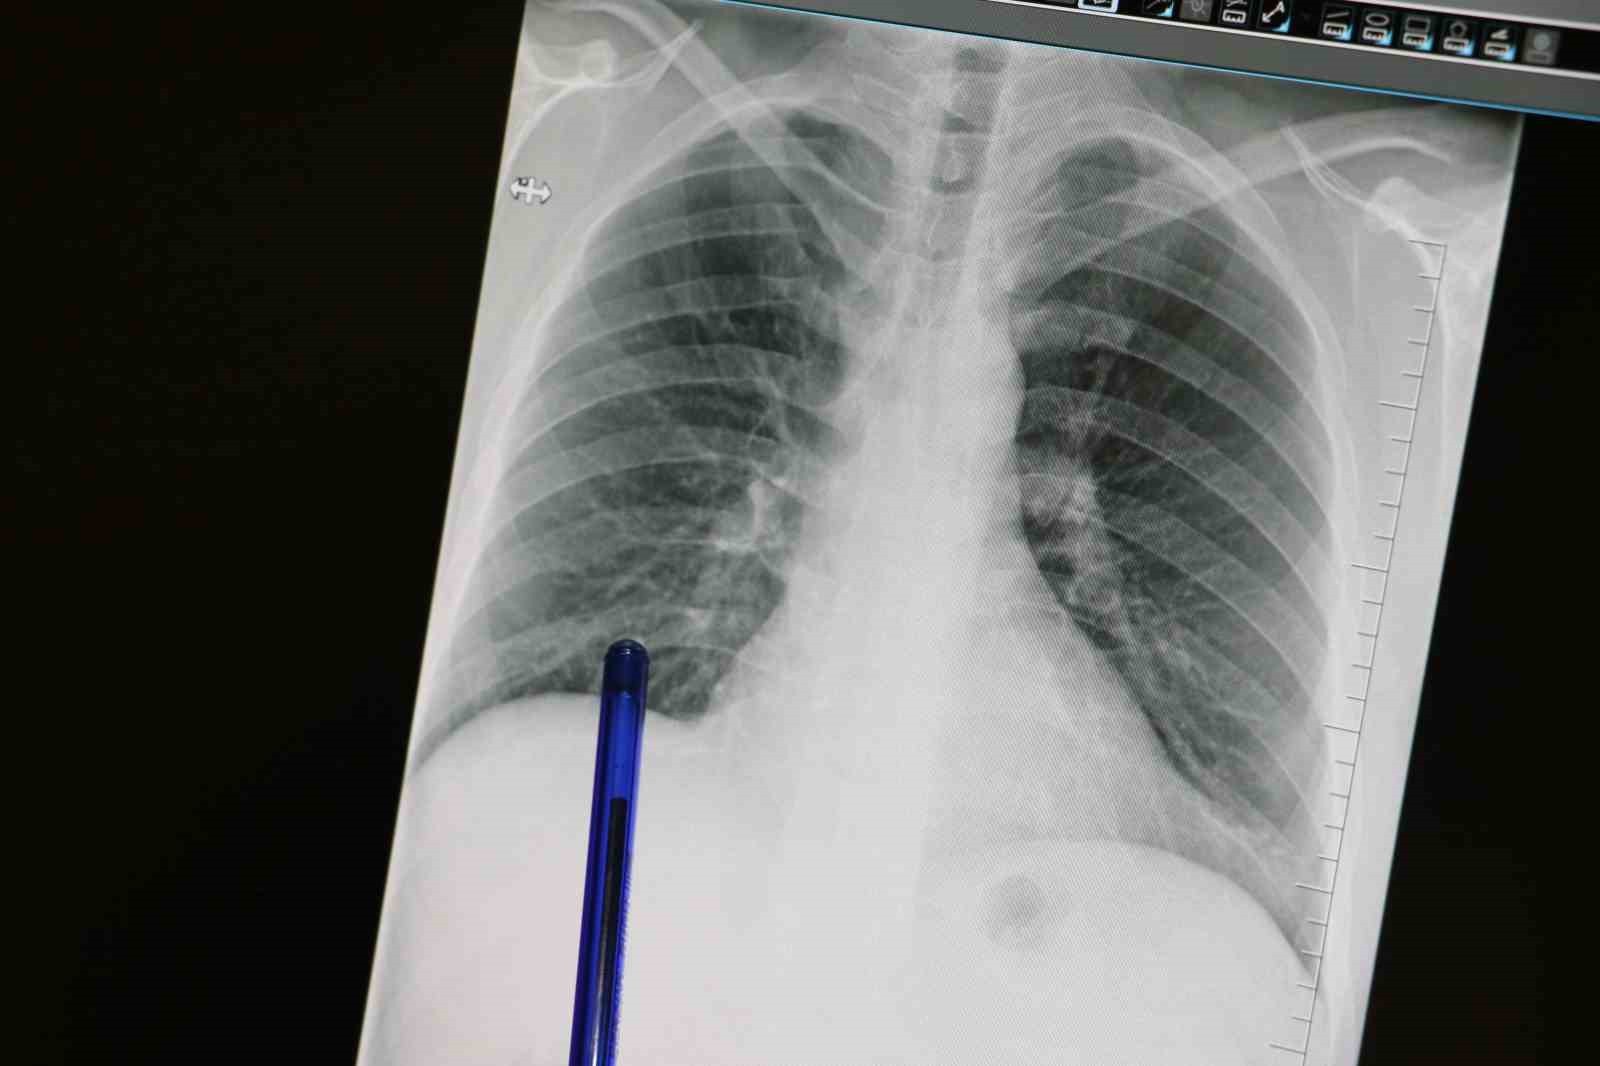

Basit belirtiler akciğer kanserinin habercisi olabilir

Medicana Sivas Hastanesi Göğüs Hastalıkları Uzmanı Dr. Büşra Yayla Yerlikaya, öksürük ve balgam çıkarma gibi günlük hayatta basit sayılan belirtilerin akciğer kanserinin habercisi olabileceğine dikkat çekti. Kasım ayının Türkiye'de 'Akciğer Kanseri Farkındalık Ayı' olarak kabul edildiğini hatırlatan Dr. Yayla Yerlikaya, erken tanının tüm kanserlerde olduğu gibi akciğer kanserinde de hayat kurtardığını vurguladı.

Akciğer kanseri, akciğer dokusundaki hücrelerin kontrolsüz çoğalması sonucu ortaya çıkan ve diğer organlara yayılabilen ciddi bir hastalıktır. Genellikle erken evrelerde belirti vermediği için geç fark edilebilmekte ve bu da tedavi şansını düşürmektedir. En önemli risk faktörü sigara kullanımı olmakla birlikte, sigara içmeyenlerde de hastalık görülebilmektedir. Pasif içicilik, hava kirliliği, genetik yatkınlık, bazı kimyasal maddelere uzun süreli maruziyet ve ileri yaş diğer risk faktörleri arasında sayılmaktadır.

Akciğer kanserinin en sık karşılaşılan belirtileri arasında uzun süren öksürük, balgamda kan görülmesi, nefes darlığı, kilo kaybı ve göğüs ağrısı bulunur. Dr. Yayla Yerlikaya, özellikle sigara içenlerde yeni başlayan ya da karakteri değişen öksürüklerin bir göğüs hastalıkları uzmanı tarafından değerlendirilmesi gerektiğini belirtti ve ekledi: "Erken tanı her kanser türünde olduğu gibi akciğer kanserinde de hayat kurtarır."